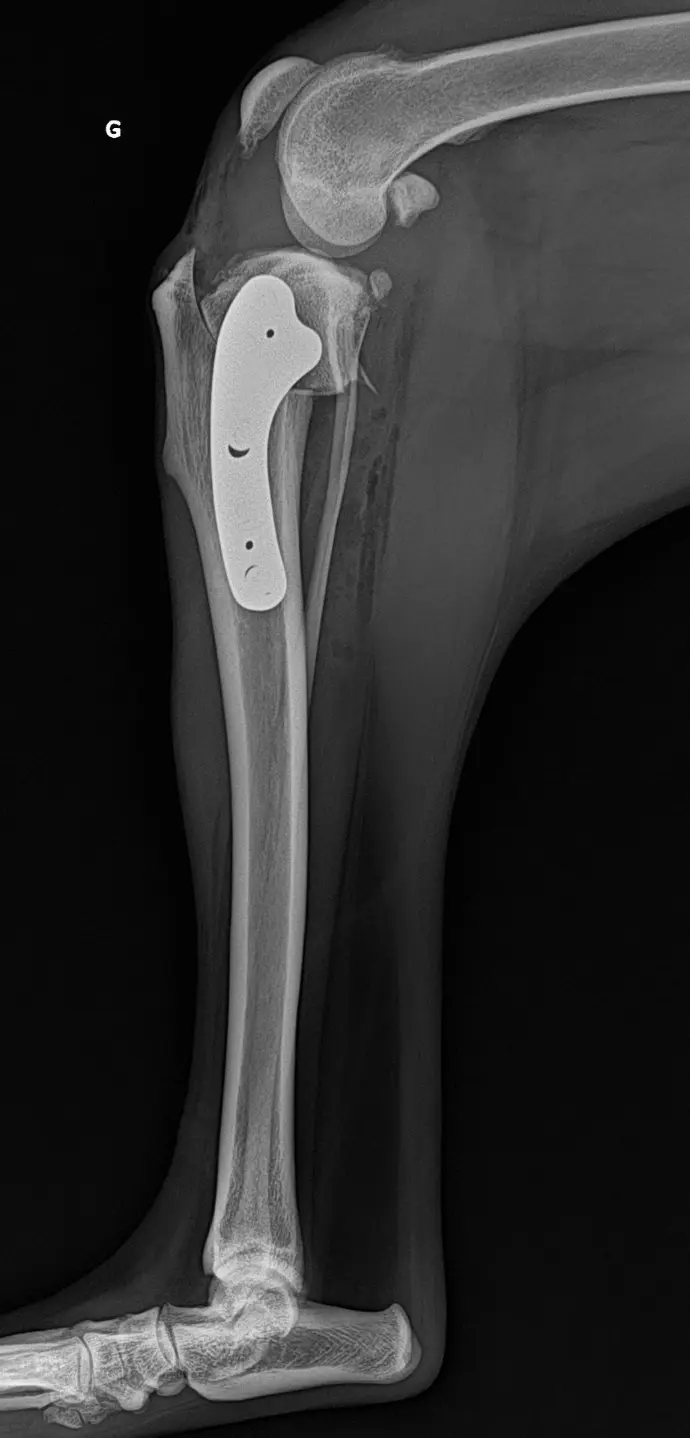

Rupture du ligament croisé antérieur

- Repos strict pendant 6 semaines : garder votre animal en cage.

- Pas de saut ni de jeux, courtes sorties en laisse uniquement pour les besoins.

- Un gonflement du tarse, un sérome et un hématome peuvent être observés et ne sont que transitoires. Contacter votre vétérinaire en cas d’anomalie observée.

- Ne pas laisser votre animal lécher le pansement ou les sutures, maintenir la collerette jusqu’au retrait des points

- Les pansements peuvent se décoller et tomber dans les prochains jours, ils ne doivent pas être renouvelés.

- Retrait des points dans 12-14 jours chez votre vétérinaire traitant.

- Contrôle radiographique dans 6 semaines (et au besoin dans 3 mois selon la cicatrisation osseuse).